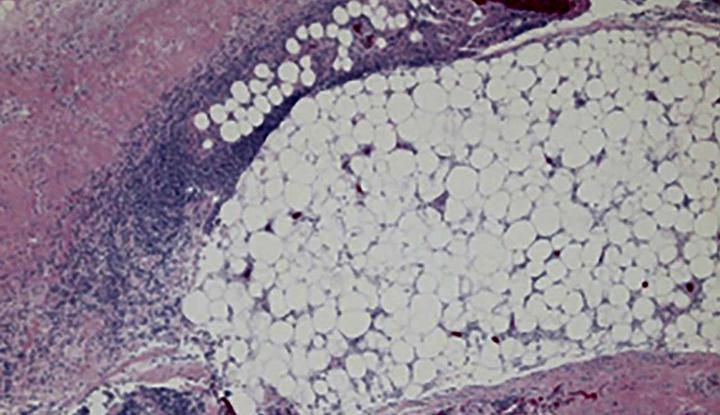

Necrotizing fasciitis is a severe rapidly spreading bacterial infection that can cause death. The word “necrotizing” refers to something that causes the death of something else. The word “fasciitis” refers to inflammation of the fascia, which is the subcutaneous (under the skin) tissue that surrounds muscles and nerves and holds everything, including fat and blood vessels, in the correct position.

Necrotizing fasciitis is a form of necrotizing soft tissue infection (NSTI). Some people call necrotizing fasciitis or any NSTI the “flesh-eating disease.” Other NSTIs are necrotizing myositis and necrotizing cellulitis.